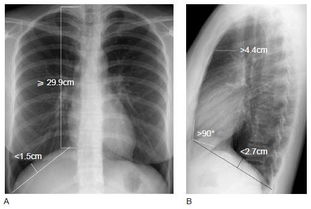

久而久之,肺泡就被這些氣體撐得越來(lái)越大,像是腫了一樣,醫學(xué)上就稱(chēng)它為肺氣腫。專(zhuān)業(yè)來(lái)講,肺氣腫是由于慢性支氣管炎或其他原因逐漸引起的細支氣管狹窄,終末細支氣管遠端氣腔過(guò)度充氣,氣腔壁膨脹、破裂而形成的肺臟過(guò)度充氣和肺容積增大的阻塞性疾病。